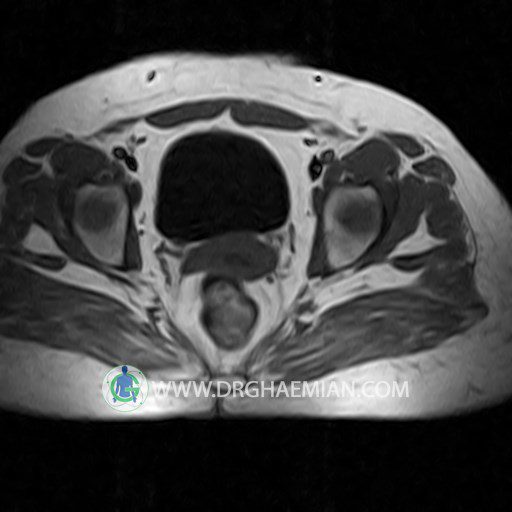

پزشکان اغلب از تصویربرداری ام آر آی برای تشخیص و درمان عارضه های پزشکی که فقط با استفاده از اشعه ایکس یا میدان مغناطیسی و امواج رادیویی قابل مشاهده است، استفاده می کنند. دستگاه ام آر آی تصاویر دقیق از ساختار های داخلی بدن ایجاد می کند. در این کیس کیست بارتولین لگن و تجمع دورمقعدی و کیست ساده ایی در تخمک چپی دیده می شود.

Technique : coronal STIR , coronal T2 , Axial T1 , axial T2 .

– Simple cyst (28×32mm) in left ovary

– Cyst like lesion (20×25mm) in right vaginal wall suggestive for bartholin cyst and perianal collection

are seen.